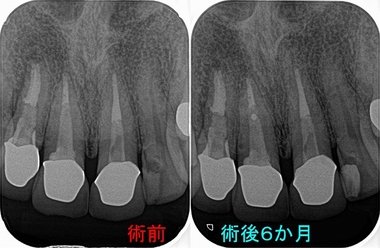

それから半年後に来院して頂き経過観察

2026 EEdental HAT (3).jpg

患者さんもあれからは膿は出てきていないようで、違和感も無くなったそう。

今回ばかりははっきりと原因歯の特定ができず、術中に確定診断出来たというレアケースでした。

何とか歯が残せそうで良かったです!